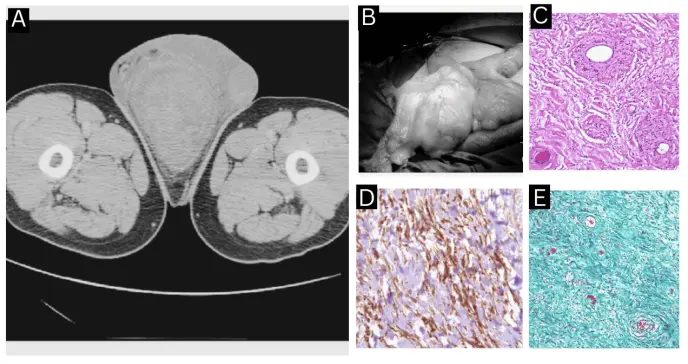

Los estudios de imagen iniciales, ecografía y tomografía computarizada, mostraron una tumoración escrotal difusa acompañada de edema y pequeñas colecciones líquidas, hallazgos poco específicos que reforzaban la impresión diagnóstica de hidrocele.

Durante el procedimiento, se identificó una masa encapsulada de aspecto lipoquístico, de 7 × 11 × 19 cm y de 576 gramos de peso, adyacente a la uretra bulbar, sin compromiso de los testículos ni adherencia a estructuras vecinas, lo que permitió una resección completa relativamente sencilla.